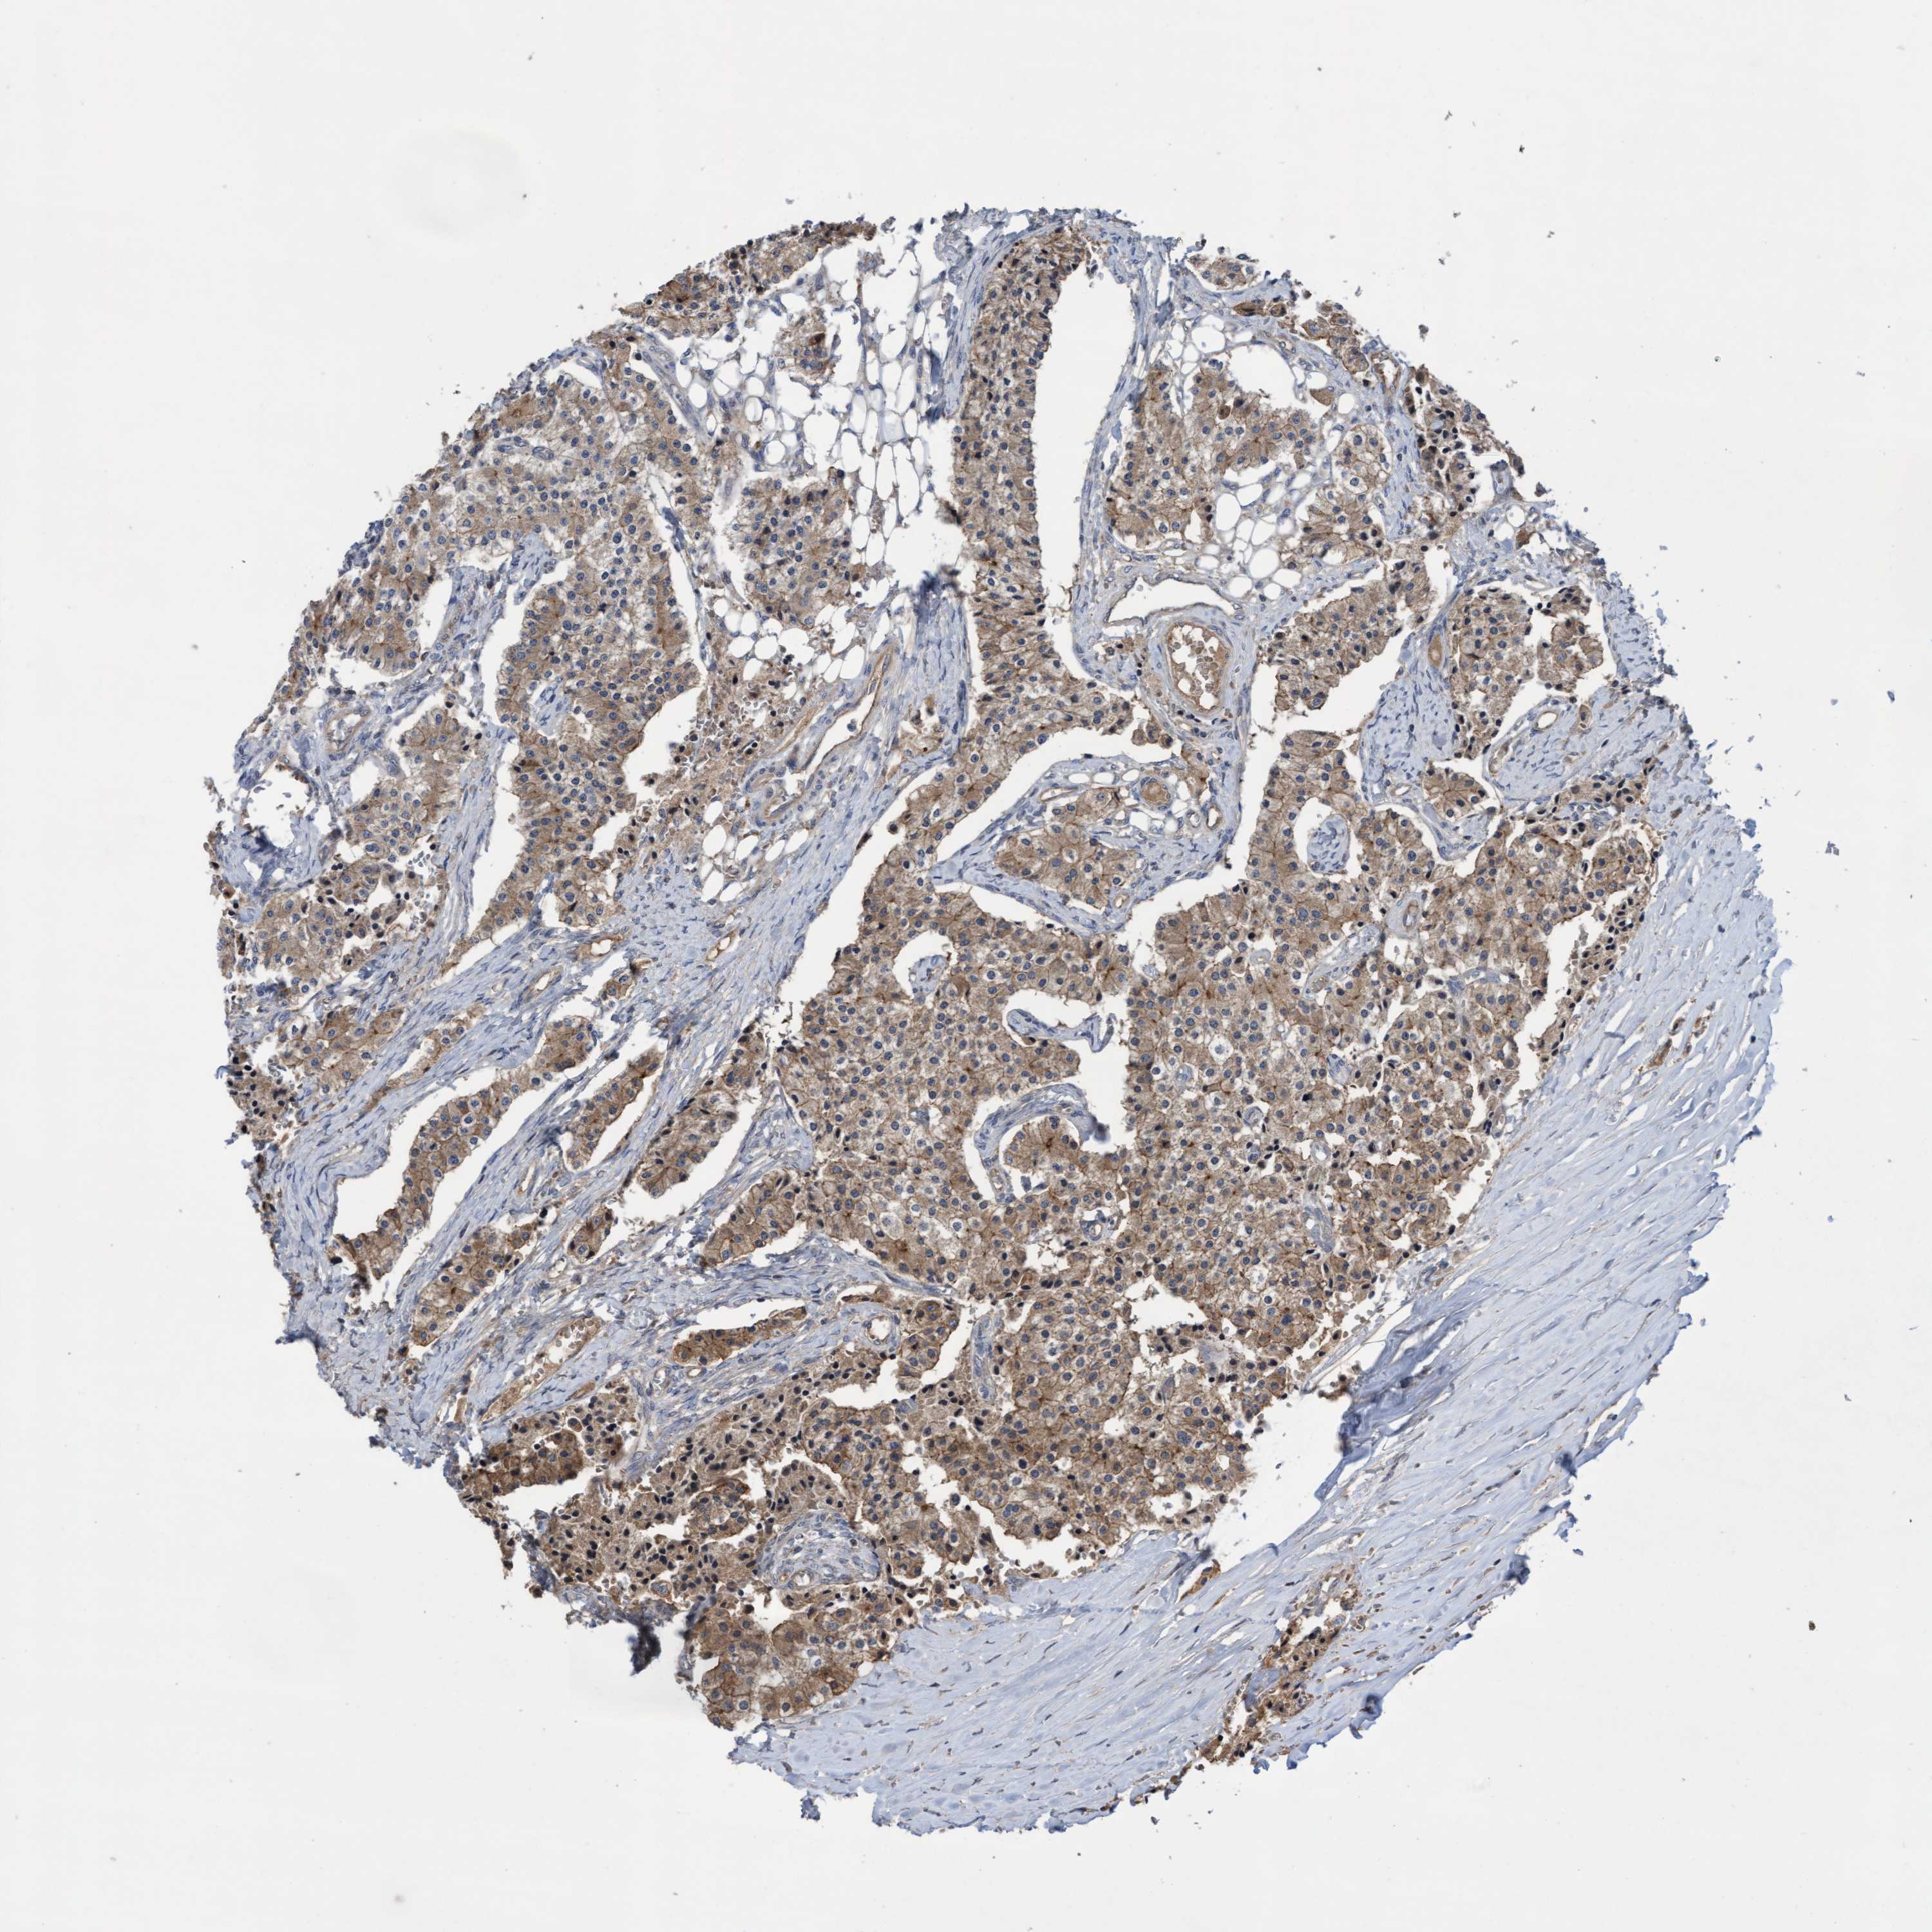

CARCINOID - Protein expressioni

A mouse-over function shows sample information and annotation data. Click on an image to view it in a full screen mode. Samples can be filtered based on level of antibody staining by selecting one or several of the following categories: high, medium, low and not detected. The assay and annotation is described here.

Antibody stainingi

Antibody staining in the annotated cell types in the current human tissue is reported as not detected, low, medium, or high, based on conventional immunohistochemistry profiling in selected tissues. This score is based on the combination of the staining intensity and fraction of stained cells.

Each image is clickable and will lead to virtual microscopy that enables deeper exploration of all samples and also displays staining intensity scores, fraction scores and subcellular localization as well as patient and tissue information for each sample.

Antibody HPA019033

Staining

High

Intensity

Strong

Quantity

>75%

Location

Cytoplasmic/membranous

Carcinoid, malignant, NOS